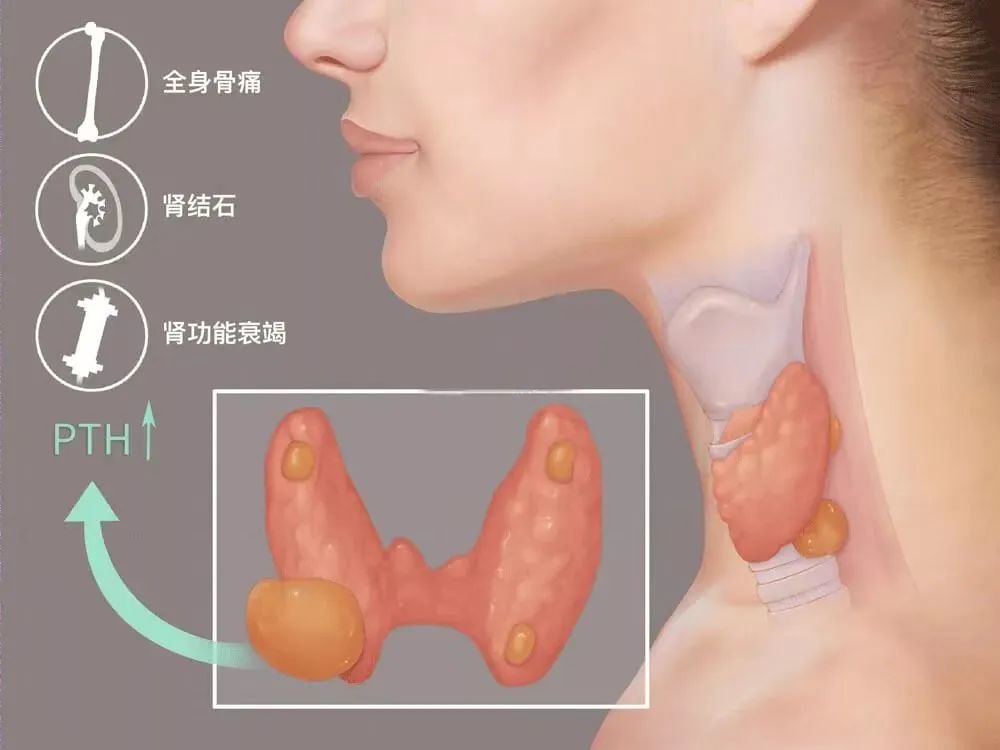

患者在得到诊断和可能引起的严重后果后非常紧张,可想到手术,又非常担心手术的风险及术后并发症,也不太接受手术后颈部的疤痕。权衡利弊,考虑到患者自身情况比较符合介入手术治疗,普外科便联系了超声医学科郑瑜主任,想利用热消融技术来代替传统手术,达到治疗效果,郑瑜主任通过二维及造影技术综合评估后,与临床医生商议了手术流程,充分术前谈话和风险告知,及时为患者进行了超声引导下甲状旁腺腺瘤的射频消融治疗。

局麻条件下,在超声实时监测下通过精细的液体注射隔离,将包块周围的神经、血管、甲状腺下极等完美的隔离保护起来,用细细的一根针进入腺瘤内,强回声的热气很快覆盖了腺瘤,一气呵成,仅仅不到10分钟便完成了整个手术,超声造影下血供丰富的高增强腺瘤结节完美的演变为无增强的“黑洞”,手术过程非常顺利,患者仅感到一点点灼热感,皮肤局部仅一个针眼,患者消融完便自行走回了病房。一天后,患者化验室检查数值回归正常水平,无其他不良反应。

超声引导下甲旁腺液体隔离及消融